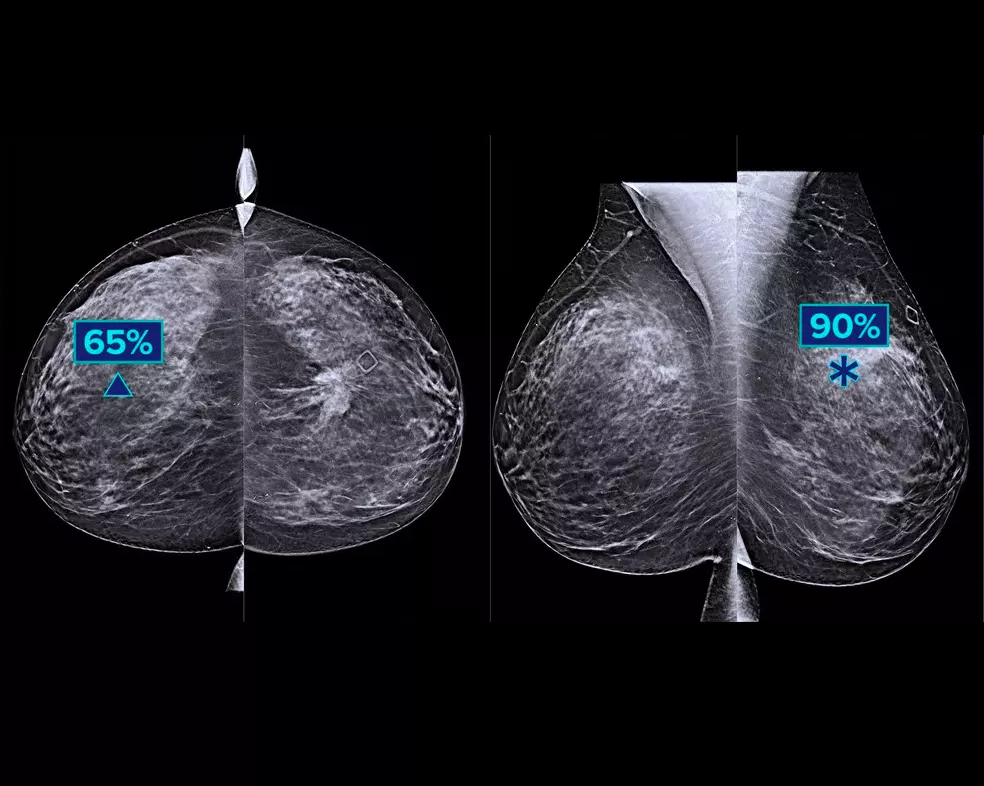

Een deep-learning algoritme is ontwikkeld om de diagnostische prestaties van radiologen te helpen verbeteren en te helpen bij de detectie van borstkanker1-3 op basis van tomosynthesebeelden die zijn verkregen met behulp van de Hologic Dimensions Mammography®-systemen. Het algoritme vindt laesies met een grote kans op borstkanker, door iedere snede van de tomosynthesebeelden te doorzoeken. Verdachte plekjes worden gemarkeerd voor beoordeling op het werkstation van de radioloog, voor grotere betrouwbaarheid van de beeldinterpretatie.

Het algoritme zoekt naar drie hoofdgroepen van verdachte laesies: calcificaties, massa's, verdichtingen en vervormingen, en eventuele combinaties van deze laesies. De output kan verschillen tussen verschillende beoordelingswerkstations.